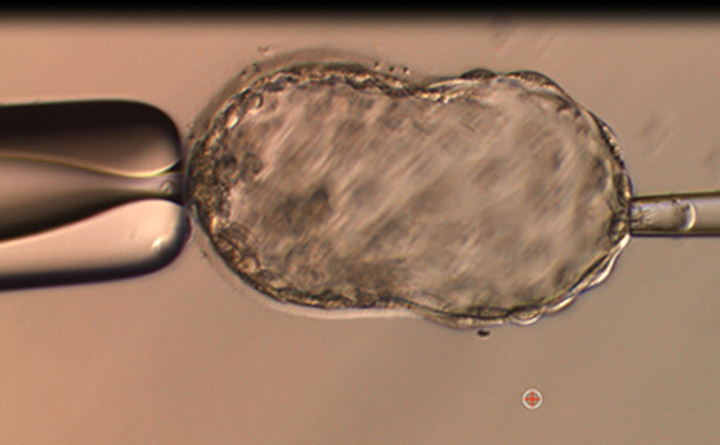

卵子细胞质内单一精子显微注射 (ICSI) 是将精子注射至一个成熟卵子的细胞质内。

此过程克服了许多受精障碍,可包括重复标准体外受精失败和严重男性因素不育,如精子数量很少和/或活动力差、多数精子形态异常、采用手术提取精子等的受精。

ICSI 是一种行之有效的显微注射技术,是患者治疗不孕不育的其它选项。

标准的体外受精涉及把算好数量的精子放入含有采集卵子的每个器皿中。 ICSI 或 PICSI 的操作步骤非常不同,它涉及我们的专家把每个精子注入每个卵子内。精子和卵子结合后,在同一个培养皿中共同培养过夜后,可观察受精情形希望出现受精。